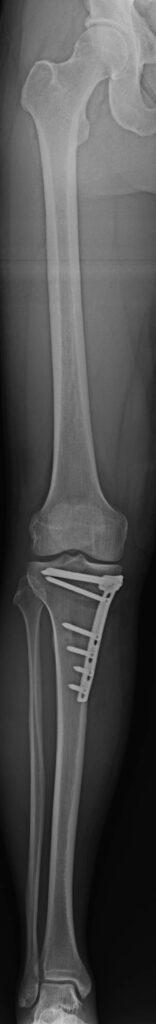

Varus-Fehlstellung (O-Bein)

Um Achsenfehlstellungen, wie O-Bein- und X-Bein-Fehlstellungen, welche zu einer Fehlstellung des Knies führen, zu diagnostizieren, müssen primär klinische Untersuchungen erfolgen: die Untersuchung des Gangbildes, des Bewegungsumfangs und der Beinachse sowie Tests rund um den Meniskus. Nach der klinischen Untersuchung können technische Untersuchungen erfolgen: Achsenfehlstellungen der Beine werden mithilfe eines MRT diagnostiziert. Des Weiteren können Ganzbeinaufnahmen im Stehen und Röntgen des Kniegelenks in zwei Ebenen Aufschluss über das Ausmaß der Fehlstellung liefern. Ergänzend wird in manchen Fällen eine präoperative Arthroskopie durchgeführt.

Um eine Achsenfehlstellung der Beine zu korrigieren, muss zumeist ein kleiner Eingriff vorgenommen werden. Dieser Eingriff kann im Rahmen eines 3-tägigen Spitalsaufenthalts durchgeführt werden und zieht meist nur eine Spinalanästhesie oder eine Larynxmaskennarkose nach sich. Liegen spezielle Fragestellungen in Bezug auf Ihre Fehlstellung vor, ziehe ich bei manchen Eingriffen ein Navigationssystem hinzu, damit die Achsenverhältnisse Ihrer Beine weiter optimiert werden können.